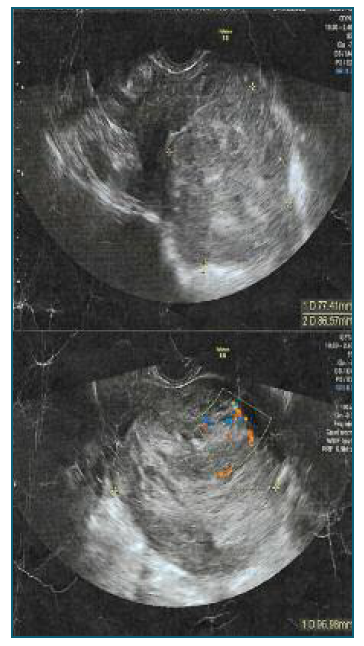

We present the case of a 50-year-old Caucasian woman admitted for elective surgery due to a rapidly growing uterine leiomyoma. From her background, she was a nulliparous woman, with non-medicated dyslipidaemia and a BMI of 19. She had no previous surgeries or smoking habits. Regarding family history, she has two paternal female cousins with breast carcinoma. In the history of the current disease, the patient mentioned irregular menstrual cycles with 5 months of evolution, which led her to go to the gynaecology emergency department for an abnormal uterine bleeding one and a half month before surgery. In this episode, a transvaginal ultrasound examination identified a polymyomatous uterus (the largest leiomyoma with 60*60 mm) and mild anaemia (Haemoglobin 10.5 g/dl), and she was medicated with desogestrel and oral iron. One week after going to the emergency department, the patient scheduled a private gynaecology appointment. In the office evaluation, the aforementioned leiomyoma had 77*86*96 mm in dimensions, a FIGO classification type 1-6, vascularization score 2 (Figure 1), but the patient didn’t present the previous examination and a subsequent reassessment was scheduled. A month later, due to maintaining the abnormal vaginal bleeding, she contacted her assistant gynaecologist who, upon reassessing, found an increase in the dimensions of the uterine mass, being urgently referred to the gynaecology oncology department and, after discussion in a multidisciplinary team, surgery was scheduled to the following week.

Figure 1 Ultrassound images of the tumour, with dimensions of 77*86*96 milimiters, and vascularization.